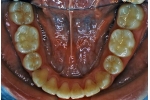

| 治療中